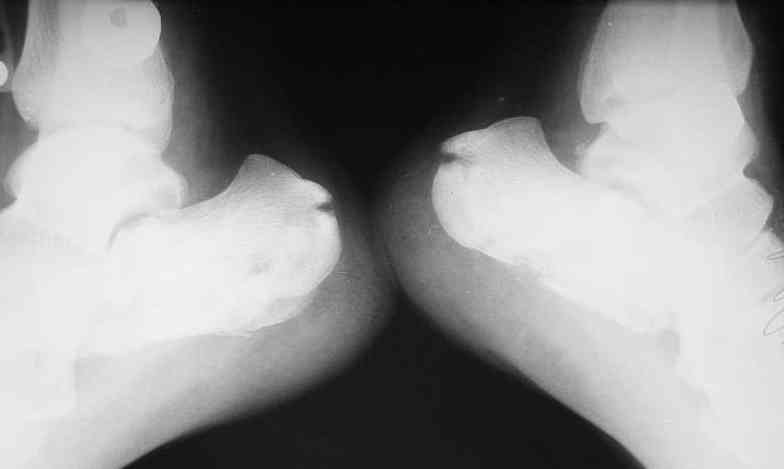

> Перелом левой седалищной кости без смещения с нарушением

> функции тазовых органов.

Нарушение функции тазовых органов связано с переломом седалищной кости без смещения??? ...или это опечатка, и функция тазовых органов относится к спинальному повреждению? Тогда, почему нестабильный перелом L3 - неосложненный?